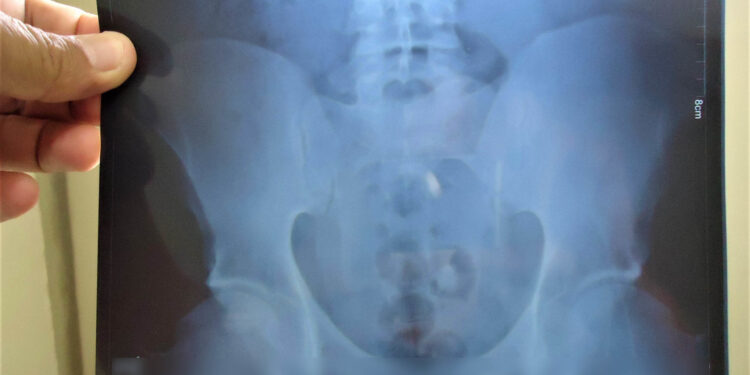

O flagrante aconteceu quando as mulheres passavam pelo aparelho (Body Scann), raio-x. Uma delas estava com um pacote de drogas no órgão genital, e as demais com entorpecentes no estômago. .